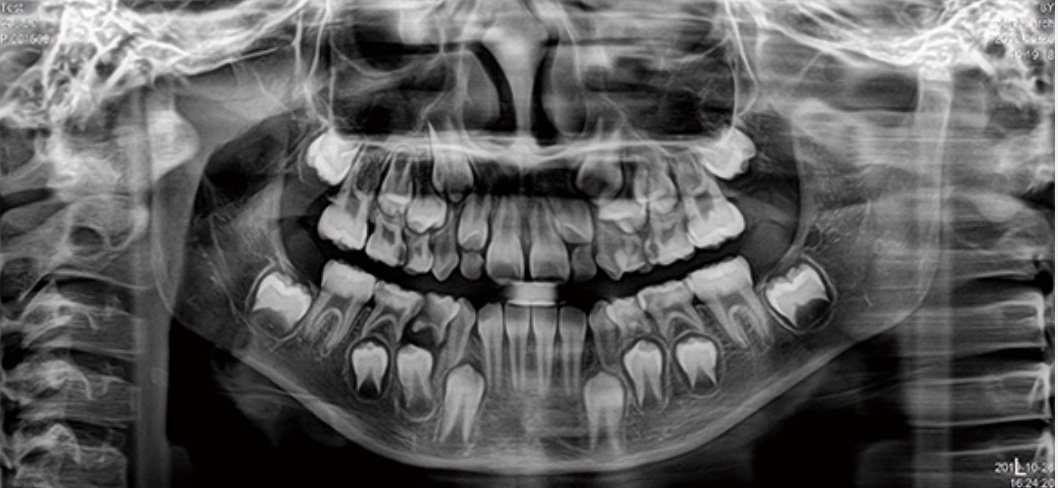

Panoramica de alta definición

La CBCT multifuncional FUXI ofrece a los usuarios una variedad de modos de imágenes panorámicas, incluido el modo estándar, el modo para niños, el modo especial, imagenes de partición, etc., para satisfacer los requisitos de imágenes de diferentes formas de arco mandibular y diferentes ubicaciones clínicas.

Modo infantil